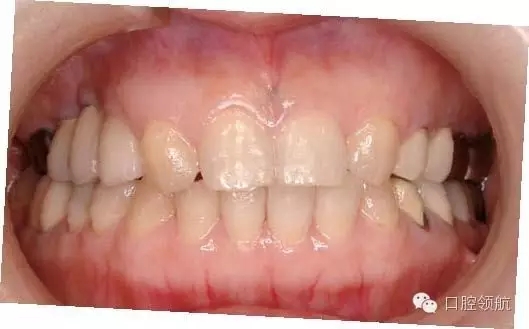

圖7 術(shù)后周圍黏膜的變化  術(shù)后4個月的口內(nèi)像  種植體周圍未見炎癥表現(xiàn)

圖9 治療結(jié)束后7年6個月的口內(nèi)正面像

圖10 治療結(jié)束后7年6個月的口內(nèi)腭側(cè)像